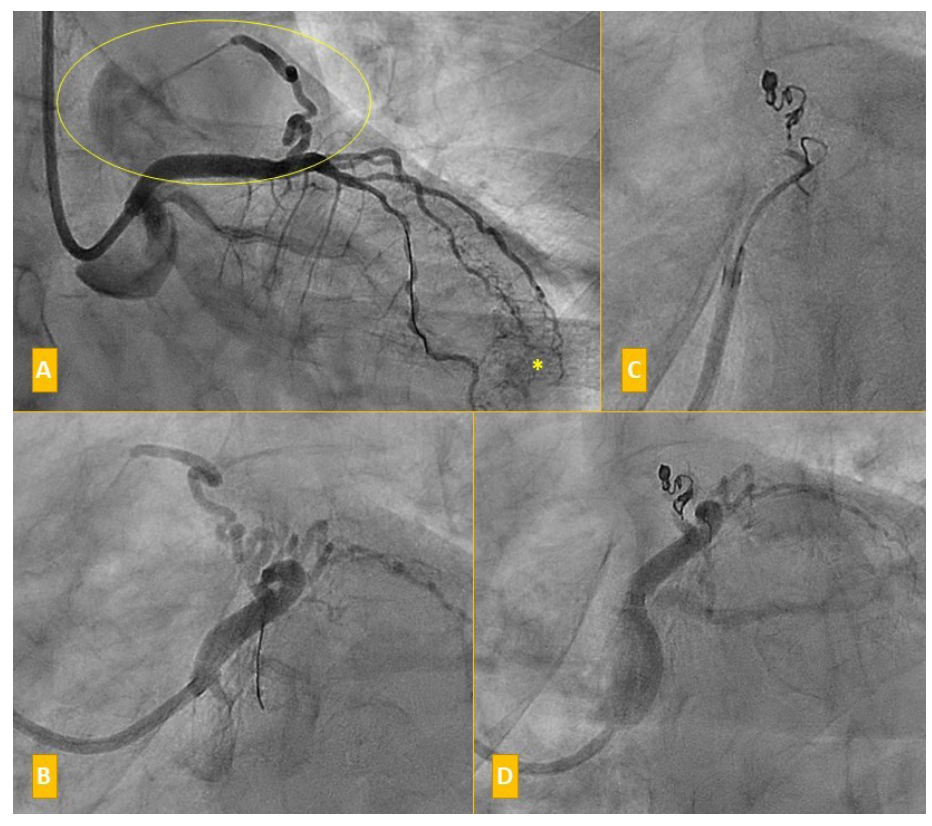

A coronary angiography showed epicardial coronary arteries without significant angiographic stenosis. However, a 2.5-2.75 mm-diameter fistula was observed communicating the proximal portion of the left anterior descending (LAD) coronary to the pulmonary trunk, with an angiographic great debit (Figures 1A, 1B; Video Series). There were also multiple microfistulas to the ventricle (Figure 1A). Given the demonstrated ischemia in the stress test, closure of the fistula with coils was indicated.

We performed right radial access and placed a safety wire on the LAD. A 2.7-Fr x 130-cm Progreat microcatheter system (Terumo Europe NV) was advanced to the medial portion of the fistula. Four Interlock coils (two 2 x 40-mm 2D-Helical coils and two 2-3 x 30-mm Diamond coils; Boston Scientific) were deployed (Figure 1C; Video Series). We observed occlusion of the fistula immediately (Figure 1D; Video Series). After discharge, the patient remained stable, with a clear improvement in her symptoms.